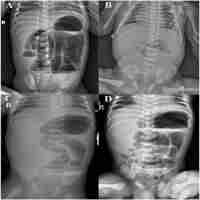

Abdominal Cocoon Secondary to Meconium Peritonitis in a Neonate: A Case Report

| Abstract | Abdominal cocoon is a complete or partial encasement of intestines and rarely viscera by a fibrocollagenous sac which is usually formed by a nonspecific chronic inflammatory reaction. We report a case of abdominal cocoon in a 2-day-old neonate presenting with intestinal obstruction. |